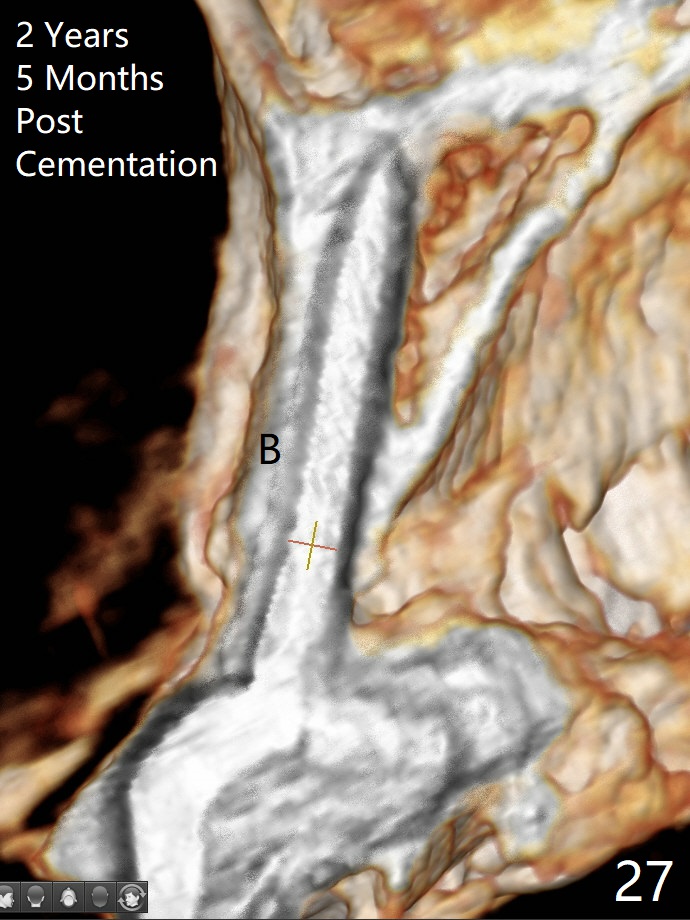

Since the ridge at #7 is ~ 4 mm, a 2.5x14 mm 1-piece implant is placed (Fig.8) after 1.2 mm (Fig.7), and 1.5 mm drills at 12 mm and 2 mm drill at 8 mm. Later the implant is placed deeper (Fig.10). There is no bone loss 7 or 12 months postop, respectively (Fig.11,12). After Diode gingivectomy, there is papillary formation (Fig.13). No provisional is provided after impression (with the abutment torqued at #6) for oral hygiene. With access holes at #6 and 7, crowns are bonded with minimal residual cement (Fig.14 <, which is removed later). There is no hard (Fig.15,16) or soft (Fig.17 *) atrophy 26 months postop, i.e., 13 months post cementation, due to the presence of socket shield (Fig.15 <, as compared to Fig.1). In fact the tooth #8 has mobility and fremitus (short root/poor crown/root ratio, Fig.16); occlusal adjustment is done 13 months post cementation. The crown is dislodged 2 years 1 month post cementation; a prefabricated post is being tried in (Fig.18). There is no atrophy, bone loss or infection at #6 (with socket sheath (*)) or 7 two years 5 months post cementation (Fig.20-27).